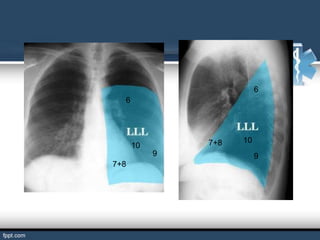

BRONQUIOS SEGMENTARIOS

Son ramificaciones de los bronquios lobulares.

El hombre tiene 18 bronquios segmentarios que estos se ramifican

en bronquiolos.

Si los bronquios segmentarios ya no se puede subdividir se le llama

bronquiolo terminal.

1

2

2       3

3

5

4   5   4

6

9   10    7       10

7       8        9

8

1+2

4

4           5

7+8   10

10

9              9

7+8